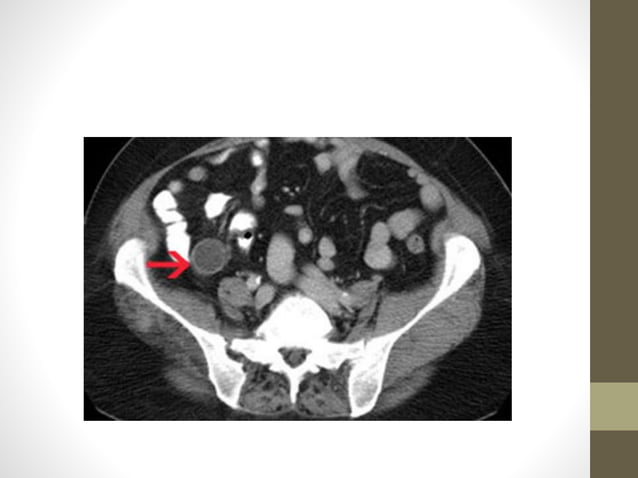

CECT image of mucocele appendix, with wide base and communicating with ...

Figure 1 from CT Features of Appendiceal Mucocele | Semantic Scholar

APPENDICEAL MUCOCELE | NR RADIOLOGY

Appendiceal Mucocele: CT - Sumer's Radiology Blog

Imaging Features of Appendiceal Mucoceles and It’s Complications ...

Predicting Underlying Neoplasms in Appendiceal Mucoceles at CT: Focal ...